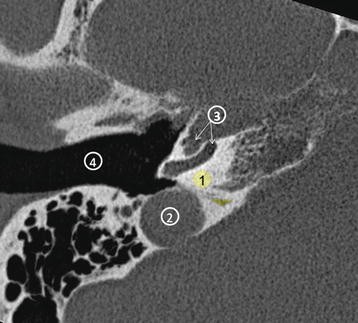

Ct scans can help determine a diagnosis early. Ct and mr of temporal bone malignancies primary and. Ct scan of normal temporal bone, photographed in bone window.